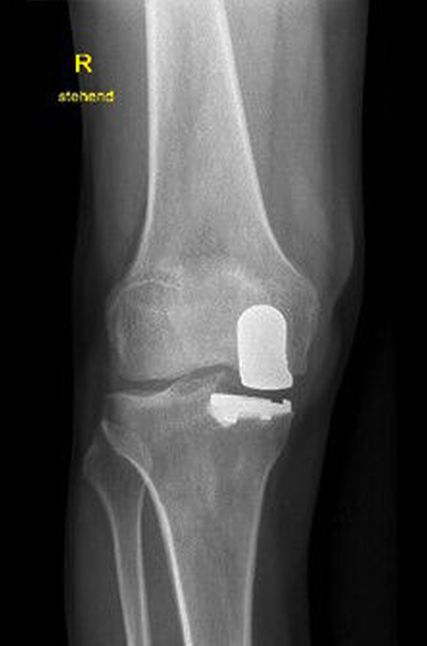

Abb. 3: Postoperatives Bild nach Implantation einer medialen Hemischlittenprothese

Ein 62-jähriger Patient stellte sich im März 2025 mit belastungsabhängigen Knieschmerzen rechts vor. Im MRT zeigte sich eine Läsion des medialen Meniskus, sodass in Zusammenschau mit dem positiven Meniskuszeichen in der klinischen Untersuchung eine partielle Meniskektomie durchgeführt wurde. Die postoperative Phase verlief zunächst unauffällig. Der Patient berichtete über ein beschwerdefreies Intervall von rund sieben Wochen. Anschließend entwickelten sich jedoch erneut zunehmende Schmerzen im rechten Kniegelenk, die eine erneute Vorstellung in der Spezialambulanz erforderlich machten. Er berichtete vor allem über belastungsabhängige Schmerzen im Bereich des medialen Kniegelenks. Daraufhin wurde ein Ganzbeinröntgen zur Beurteilung der Beinachse durchgeführt, hier zeigte sich eine varische Beinachse mit 5 Grad Varus (Abb.1). In der ergänzend durchgeführten MRT-Untersuchung konnte medialseitig eine ausgeprägte Nekrosezone am medialen Femurkondyl nachgewiesen werden (Abb.2). Schlussendlich wurde aufgrund dieses Befundes die Indikation zur Implantation einer medialen Hemischlittenprothese rechts gestellt, die schließlich im August 2025 komplikationslos durchgeführt wurde (Abb.3+4).